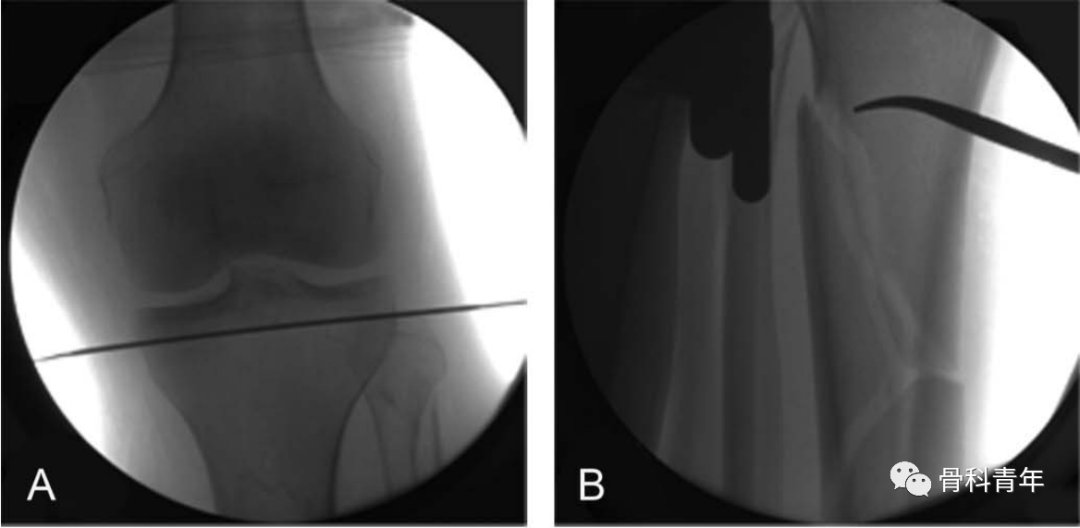

通过在胫骨平台下方1cm,平台偏后部置入一根钢丝,另一根钢丝置入踝关节软骨下骨处,钢丝连接外侧2/3碳纤维环形架,施加110kg拉力形成张力。由于钢丝非中心置入,因此在轴向撑开时,骨折断端可能会向后成角,需要在中部后方垫消毒巾,并巾钳固定。

该外架为碳纤维,术中不影响透视,且该2/3外架,将连接杆置于小腿后方,给髓内钉的内外置钉留出空间。